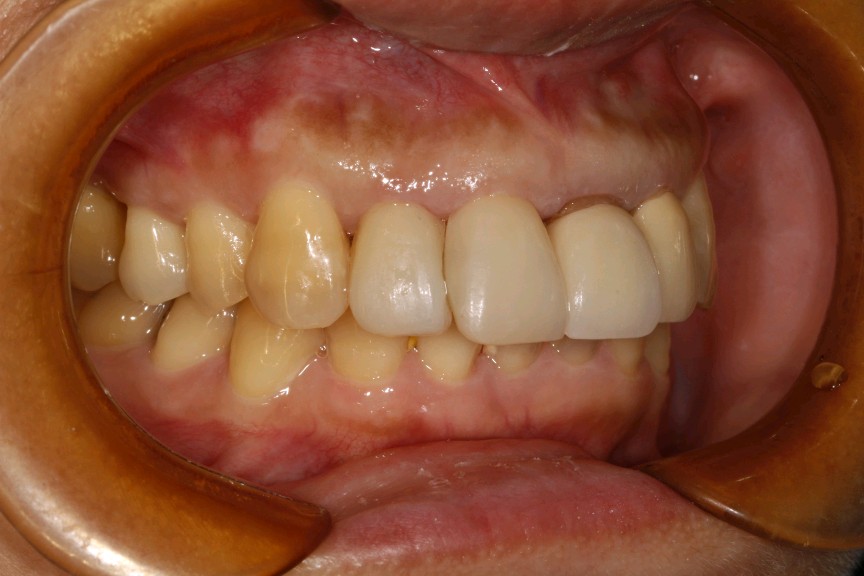

患者女,45岁。患者自述有刷牙出血症状,探易出血,探及牙周袋深度5mm,可探及袋内牙石3mm。21、22已行根管治疗加桩冠修复,牙龈萎缩,边缘不密合,21牙颈部楔缺。中切牙之间缝隙较大。12邻面部分充填物。。X线示根尖无阴影。患者自觉前牙不美观,要求重新修复。

治疗计划:1、牙周治疗。2、21,22饵激光拆除牙冠。清理基牙,重新预备,西诺德全冠修复。3、11、12贴面修复。